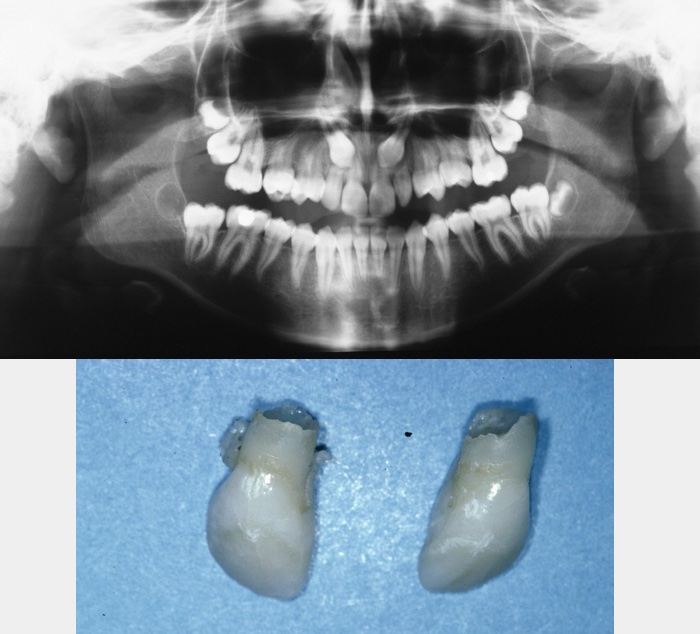

Occasionally severe infraocclusion occurs. This is defined as when the marginal ridge of the primary tooth is below the level of the gingival margin. In these situations, the tooth should be extracted. These extractions are usually uneventful with the area of ankylosis not causing any significant problem. Occasionally, when the infraocclusion occurs early, the deciduous tooth totally submerges and not only prevents eruption of its successor but may cause adjacent teeth to tip towards the infraoccluded tooth, restrict development of the dentoalveolus (leading to lateral open bites), or, because of its continued communication with the oral cavity, may lead to decay, periodontal disease or periapical pathology. In these cases, it will be appropriate to remove the tooth and the technique employed will depend on accurate localization of the tooth by clinical and radiographic examination (Figure 11 and Figure 12).